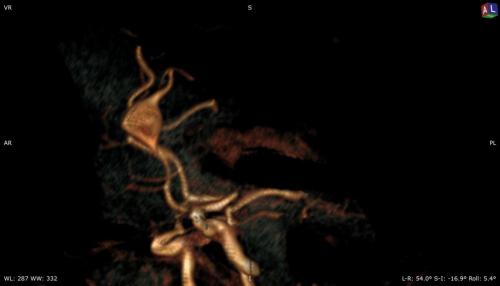

Aneurysma re. 7 mm Darstellung in einer DSA (digitalen Subtraktionsangiographie) links nur ein 2 mm „Baby-Aneurysma“ Im MRT war zuvor das linke Aneurysma aufgefallen, die Auflösung einer DSA ist technisch im MRT nicht erzielbar, beide A. liegen in der ACM Bifurkation jeweils, das re. Aneurysma wurde erfolgreich operiert, das linke Aneurysma wird kontrolliert.